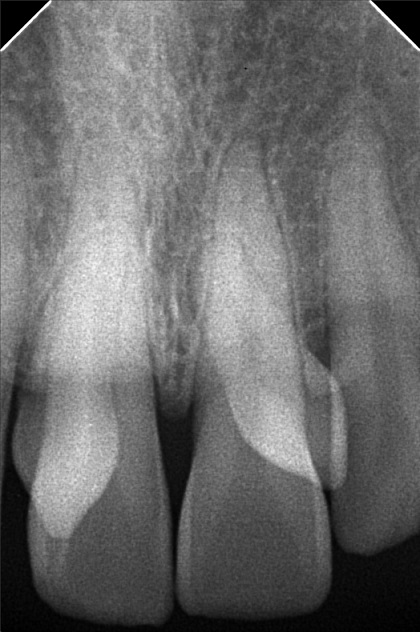

- 8/20/22- Checkup of supernumerary tooth (mesiodens), suggested extraction and ortho tx 9/10/22 - EXO SUPERNUMERARY (MESIODENS) #12, #22, Given post op instructions, prescribed mefenamic acid 500mg for pain 11/04/22-installation of braces/OP 12/3/22- adj 01/07/23- ADJ 02/10/23-ADJ/LC 04/15/23- Removal of Coil Spring/ same wire/ Chain #13-16/ #23-26 05/16/23- Ortho/U - SS- 18 L - Same wire/Ligature wire #12-#22/Chain #13-#16; #23-#26/Fox class 2 07/14/23- same wire reattachment 34 08/18/23- Chain Upper/ Box elastic 14-15 to 44-45/24-25 to 34-35 09/16/23- same wire/ chain U 10/14/23- 16x16ss U 18ss L 11/15/23- ADJ 16x16 U 16x 16 L 12/09/263- same wire, Extrude #11,21 01/13/24 same wire RW on #43 distal chipmunk 13-43 02/10/24- adj 18ss upper LC 37- Occlusal/ mesial class II 03/16/24 Adj stabilation of bite same wire l;ast wire next meeting 16x22 NITI 04/27/24 16x22 NITI cross elastic on posterior all Q 05/01/24 reattachment #26 05/18/24 Adj same wire LC #36 Occlusal #11 mesial (in) #23 mesial (out) 07/27/24 Adj same wire ligature wire 08/24/24 same wire chain U/L 10/19/24 removal of brace with retainer 02/15/25 LC #16,#17 Occ+lingual pit 03/22/25 LC #26 lingual pit class II mesial OP 12/27/25 Oral Prophylaxis - light Xray LC #46 - OCC #47 - OCC #36 - Distal, Occ #37 - Mesial, Occ 01/24/26 Rx. prednisone

- napolitano_ojiah_02.jpg

- ojiah_may_napolitano.jpg